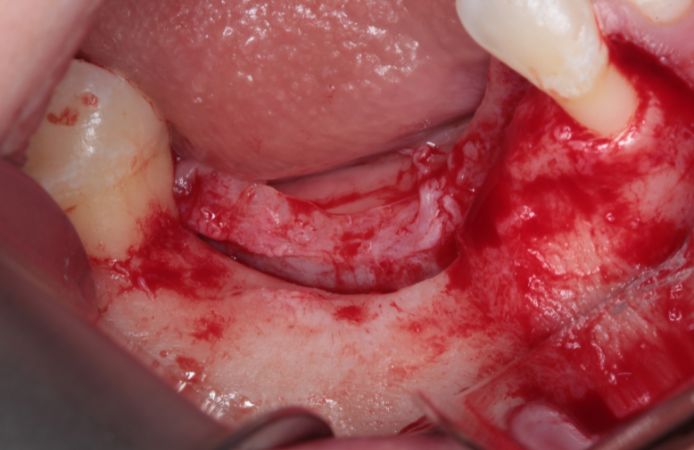

Figure 3.

Bone defect visible after full thickness flap elevation. A mid-crestal incision was performed with intrasulcular incisions. Vertical incisions were performed one tooth away from the defect.